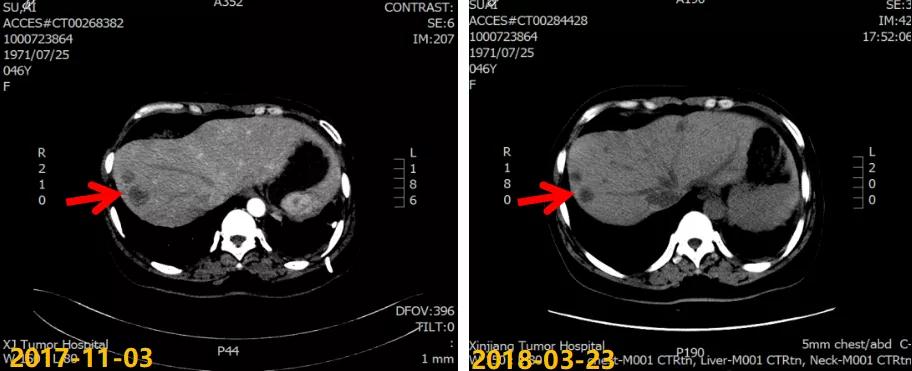

第一次病情进展: 2017-10-22患者因“气喘气憋、呼吸困难20天”就诊我院,胸水超声提示左侧大量胸腔积液,行胸水穿刺引流,查见癌细胞。2017-11-03 CT:两肺多发结节,考虑转移瘤;左侧胸膜斑块状增厚,提示胸膜转移;肝脏多发转移瘤。进一步行肝脏肿块穿刺活检,病理:ER(2+,90%),PR(3+,80%),HER2(2+),Ki-67(+,40%),FISH检测:未观测到基因扩增。

2017-11至2018-03:TX方案6周期(多西他赛120mg d1+卡培他滨1500mg po bid d1-14),化疗期间继续戈舍瑞林3.6mg ih q4w。疗效评估:前四周期略缩小但未达PR,后两周期SD,呼吸道症状明显改善。2018-04行戈舍瑞林3.6mg ih q4w联合氟维司群 500mg im q4w内分泌维持治疗,同时经MDT多学科讨论后行肝脏射频消融术。一线治疗获得36个月PFS。